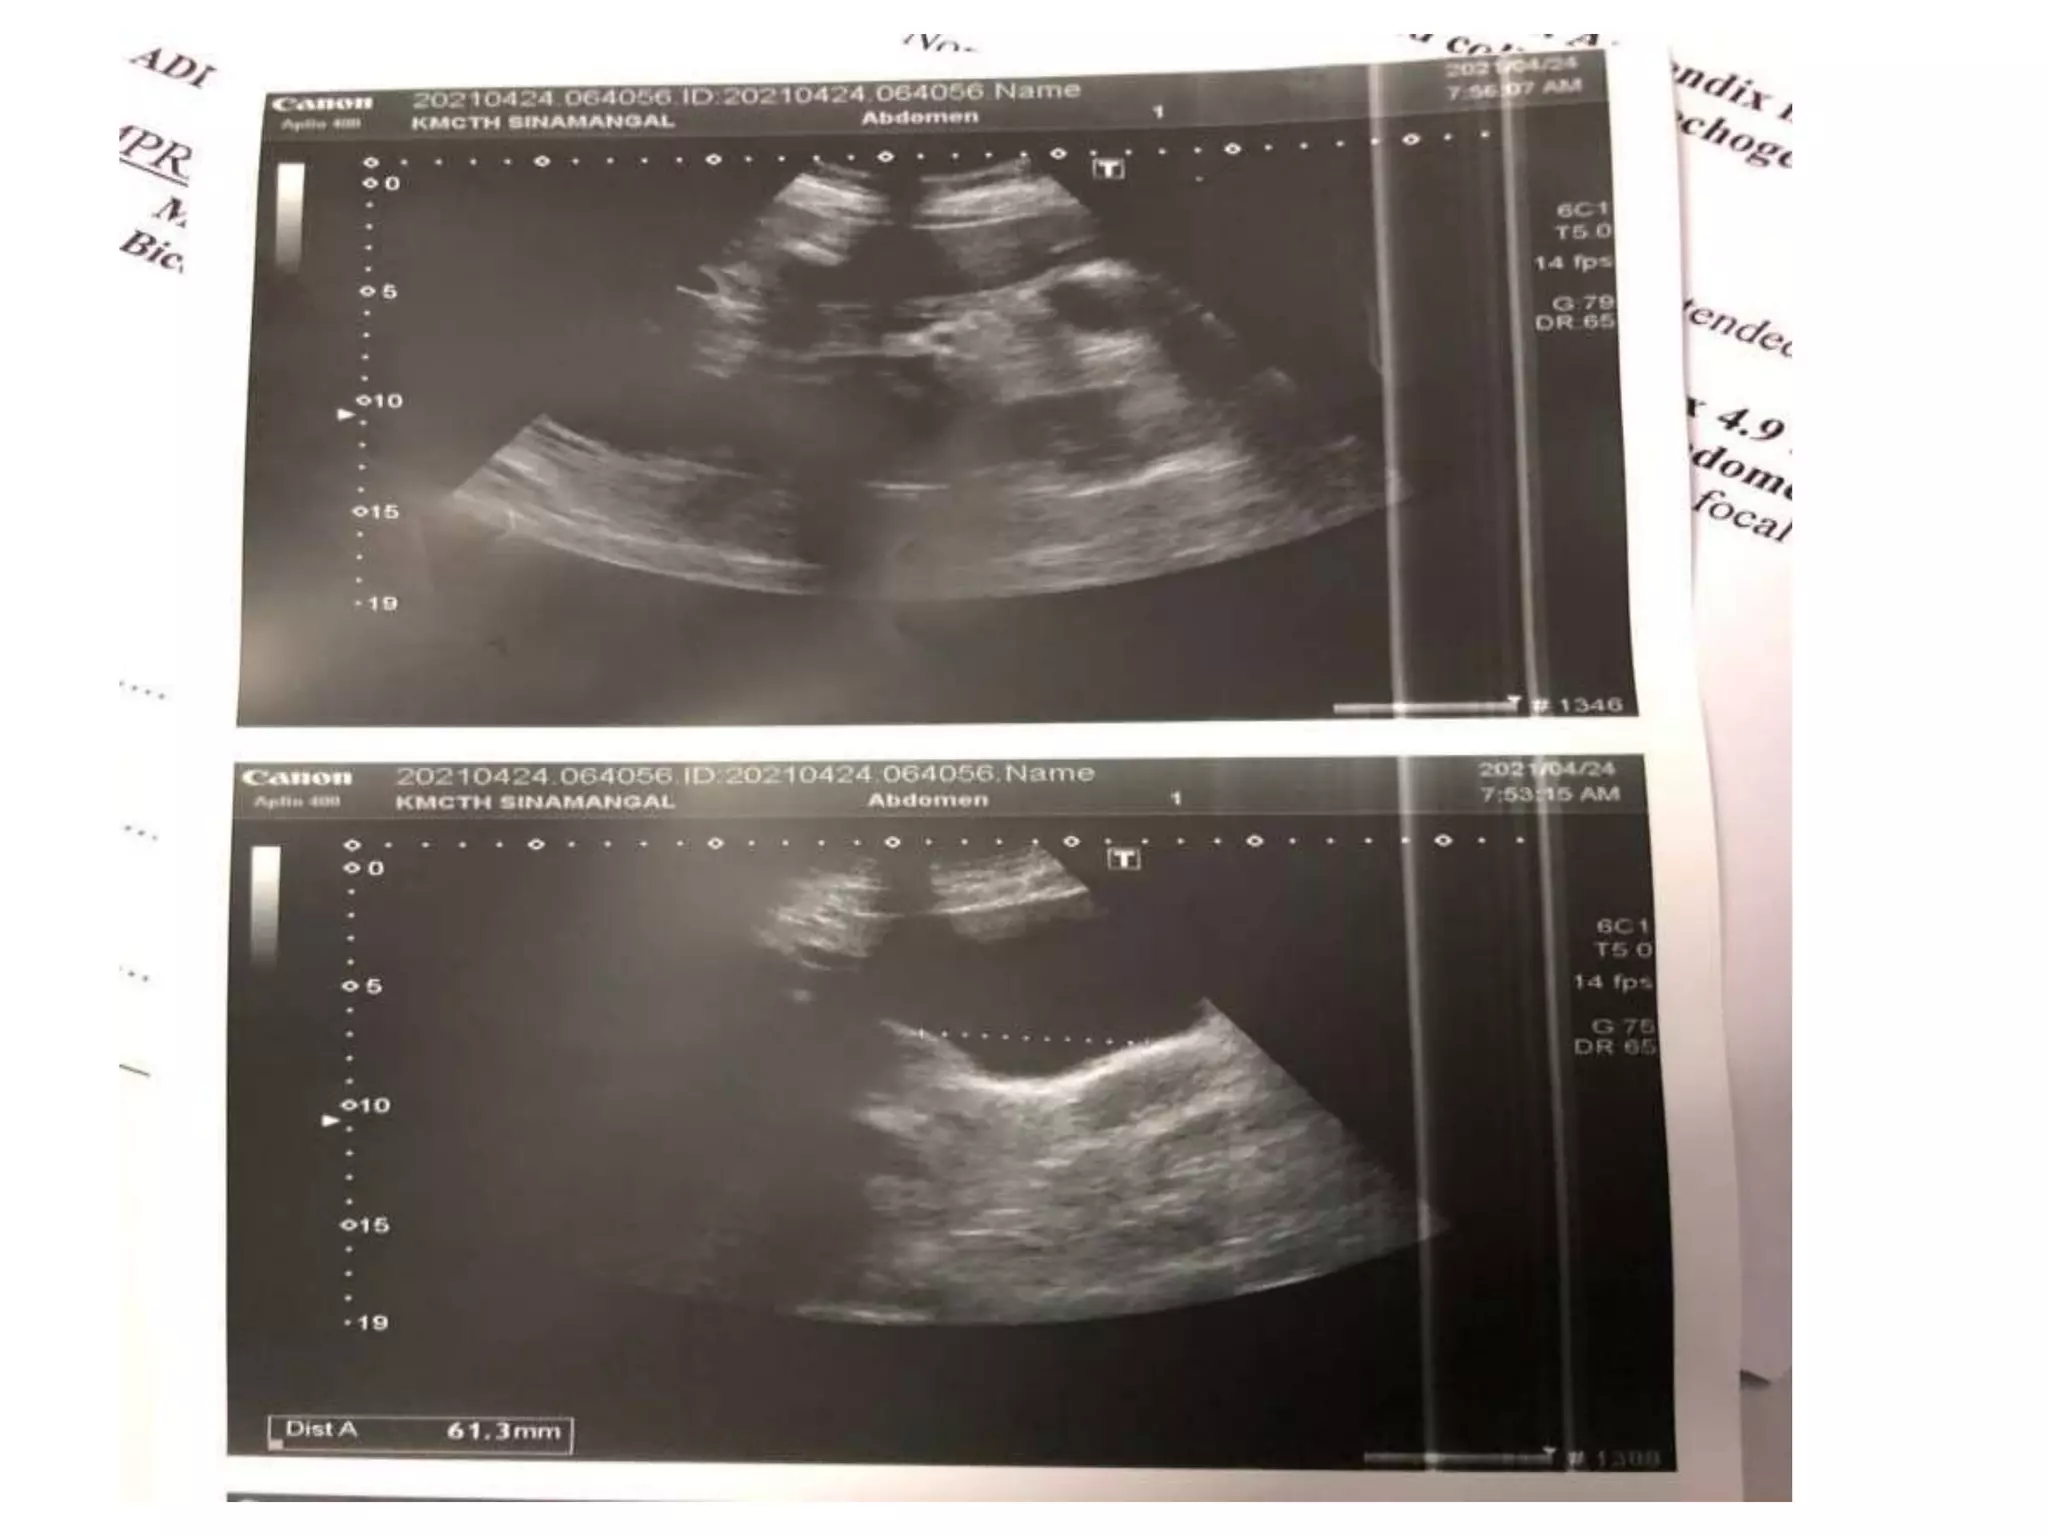

A 35-year-old woman presented with severe lower abdominal pain and difficulty urinating. An ultrasound revealed she had two separate uteruses with separate cervical canals but a normal vaginal canal, consistent with a bicornate bicollis uterus. This type of uterus is a müllerian duct anomaly that can result from interrupted development of the müllerian ducts in utero. Müllerian duct anomalies are associated with renal, vertebral, and cardiac anomalies as well as infertility and menstrual disturbances.